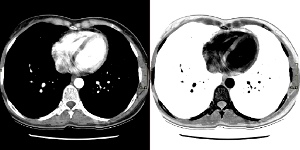

Χρησιμοποιήστε την αντιστροφή για να αντιστρέψετε τις τιμές κλίμακας του γκρι σε εικόνες.